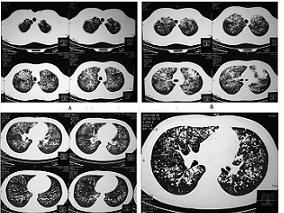

1小时条评论一、病史摘要 患者,男性,28岁,厨师。因反复咳嗽、咳痰伴胸痛1个月余,于2007年11月6日入院。患者于2007年9月21日无明显诱因出现咳嗽、咳白痰,量少,伴胸痛,自觉发热、盗汗、乏力、体重减轻、食欲差,进食后咳嗽伴呕吐,在当地医院行肺部CT检查(图20‐1),诊...